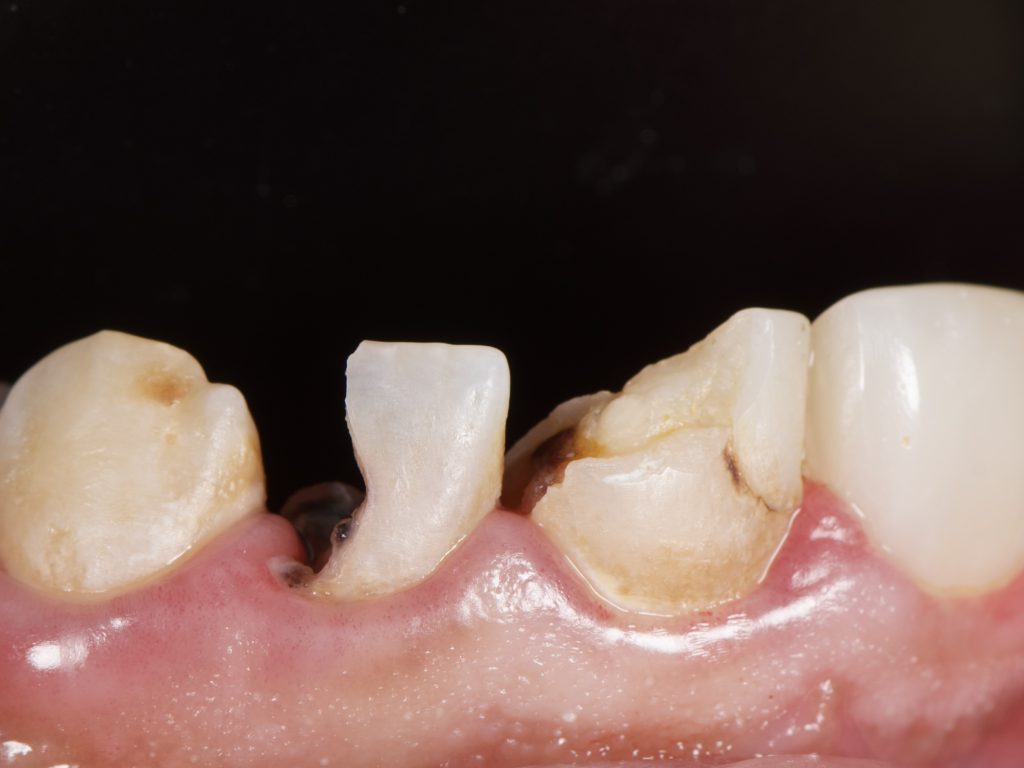

Direct composite restoration for upper anterior teeth.

Se clearfill bond, Ribbond used for dentine replacement.

Direct composite with layering technique.

2 months follow up